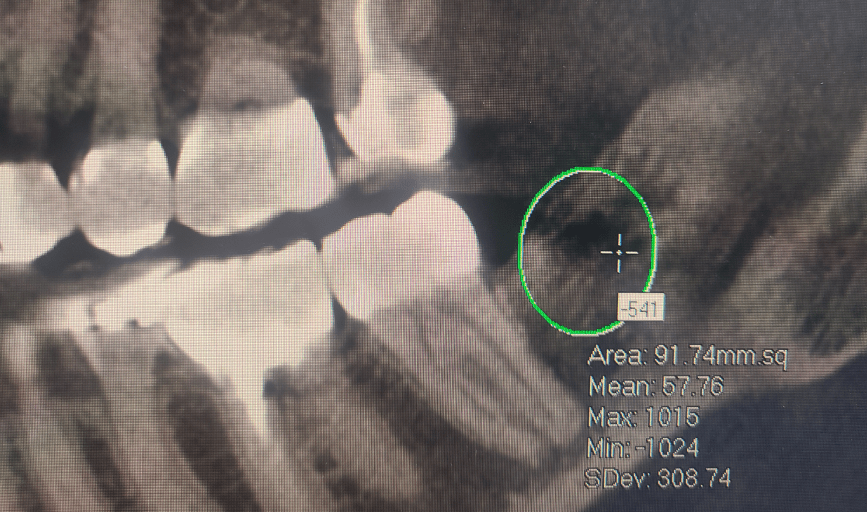

Bone cavitations could be tricky to diagnose, a simple x-ray or panoramic x-ray will not be enough. The best way to diagnose a bone cavitation is with a CT Scan or Cone Beam CT. There are specific CT Scans that can measure bone density. Bone density should not have a negative number. Readings of a (-100) or more are indicators of bone cavitation. They are usually located at extraction sites. For more information, do not hesitate to schedule a consultation with us. We would be honored to have you.